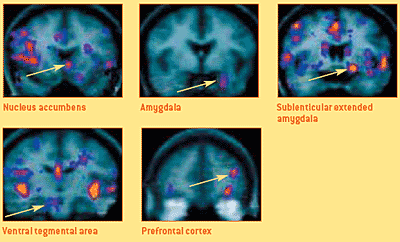

Die vier Hirnregionen des „klassischen“ (links) und aktualisiert erweiterten (oben) Lust-, Belohnungs- und Glückssystems

(Bild unten): Diese fMRI-Scans (coronale Aufnahmen, Durchsicht von vorne) zeigen zusammenfassend die Gehirne von Kokainsüchtigen nach dem Sniffen von Kokain. Die Aufnahmen bestätigen, wie unter Kennern der Sucht-, Lern-, Motivations- und Glücksforschung seit langem bekannt, die prompt aufleuchtenden Aktivitätsmuster von fünf Hirnregionen (gelbe Pfeile)10).

fMRIs von Hirnregionen des Lust- und Belohnungssystems

Copyright © 2003 by Hans Breiter, MIT, Harvard / USA

(Bild unten): Während die Gehirne der Kokainsüchtigen abgescannt wurden, beurteilten sie auch die Intensität ihrer Rush- und Craving- (Gier-) Gefühle nach Kokain, auf einer Skala, die von 0 bis 3 Punkte reichte. Beim abschließenden Vergleich kam dabei zum ersten Mal ans Licht, dass das ventral tegmentale Areal und die sublenticular erweiterte Amygdala wichtig für den durch Kokain ausgelösten Rush und die Amygdala und der Nucleus accumbens sowohl wichtig für den Rush, als auch für die Gier nach Kokain sind. Wie die folgende Grafik zeigt, klang ihre durch den Rush ausgelöste Euphorie innerhalb von 12 Minuten wieder ab, während ihre Gier (Craving) nach Kokain wieder zunahm10):